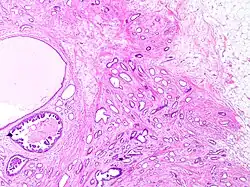

Tubular carcinoma

Tubular carcinoma is a subtype of invasive ductal carcinoma of the breast.[2][3] More rarely, tubular carcinomas may arise in the pancreas[4] or kidney.[5] Most tubular carcinomas begin in the milk duct of the breast and spread to healthy tissue around it.[6][7]

Tubular carcinomas are generally around 1 cm. or smaller, and are made up of tubules. They are usually low-grade.[2] Elastosis has been noted as common but is not present in all cases.[11]

A highly differentiated invasive carcinoma that forms well-defined tubules (containing epithelium, but no myoepithelium) and that have abundant desmoplastic fibrous stromal reaction between the tubules.